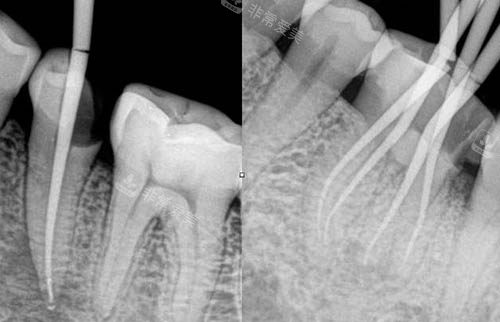

根管治疗ct照片

根管治疗动画模拟图